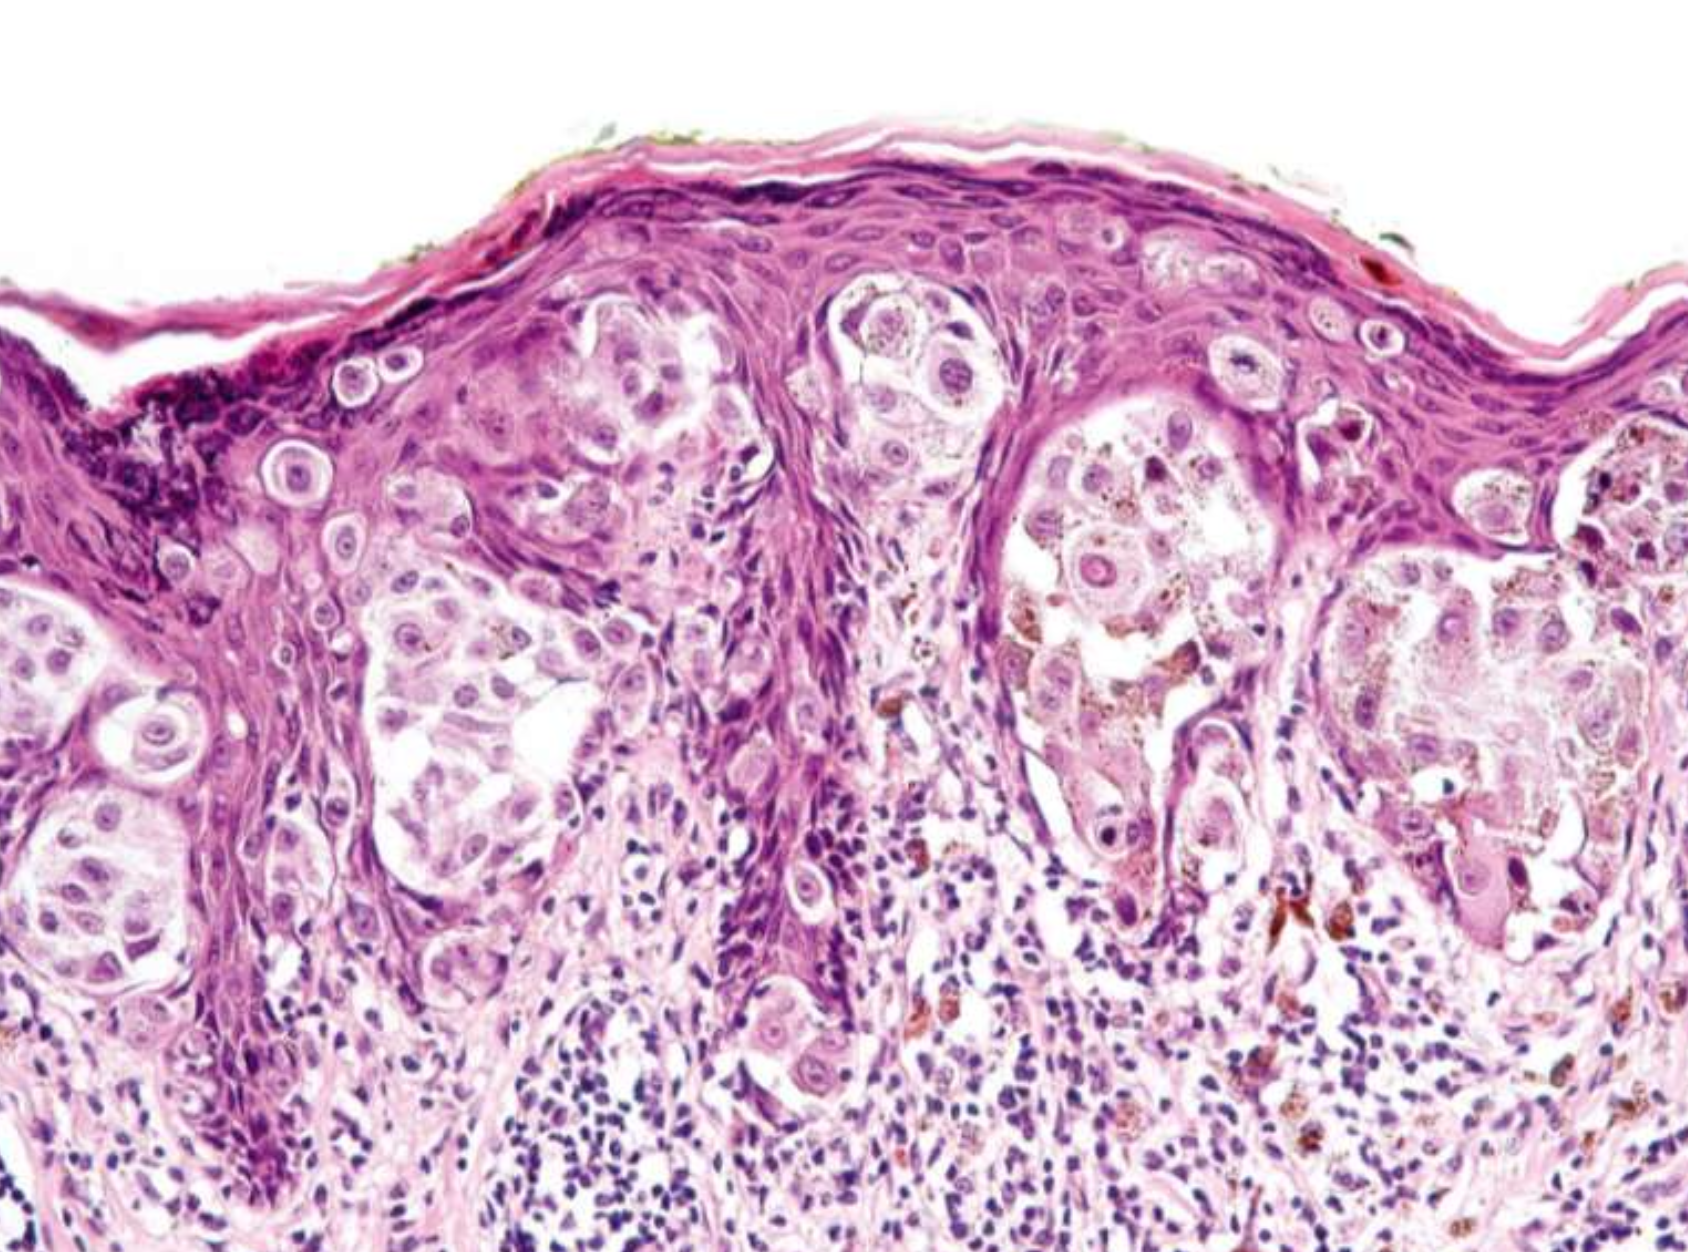

分級

根據和正常上皮的相似度及產生的 keratin 多寡來分級

- Grade I, well-differentiated: 產生正常量的 keratin

- Grade II, moderately-differentiated: 產生少量的 keratin

- Grade III, poorly-differentiated: 幾乎不產生 keratin

組織

- 中央凹陷處的邊緣會有銳角

- 坑洞內充滿角蛋白

- 不會延伸超過病灶的汗腺

- 分化成熟,但角化不良,可能 keratin pearls

- 與 SCC 很難區分 → 切